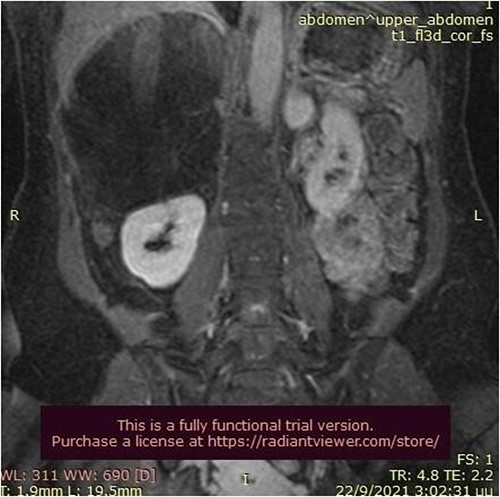

A 50-year-old woman was referred for surgical resection of a large right adrenal mass, which was incidentally found in an ultrasound scan performed for vague abdominal symptoms. Subsequently an abdominal MRI scan depicted a 16 × 15 × 6 cm right adrenal mass with characteristics suggestive of a myelolipoma, without evidence of vascular or periadrenal organ invasion (Figs 1 and 2). The patient underwent a comprehensive hormonal serum testing that confirmed a nonfunctioning adrenal mass. Because of the size of the lesion, an open operative approach was selected. Through a supraumbilical midline incision the mass was carefully dissected from the surrounding structures. It was adherent to the right kidney, the liver and the inferior vena cava without, however, compressing it. The harmonic scalper was used and clipping of the adrenal vasculature as appropriate. Intraoperatively, there was no adverse event. The specimen was removed intact and was sent for histological examination (Fig. 3). A silastic corrugated drain was inserted before closure of the laparotomy. The patient’s postoperative course was unremarkable and she was discharged on the third postoperative day. Histopathology revealed a lesion consisting predominantly of fatty tissue containing all types of hematopoietic stem cells and confirmed the diagnosis of myelolipoma (Figs 4 and 5).